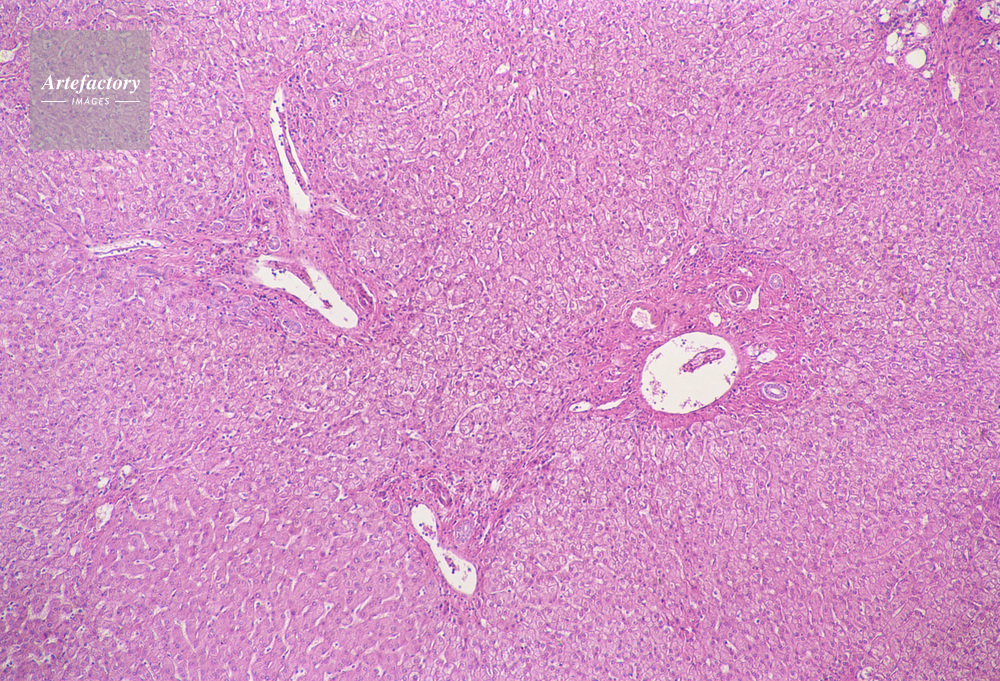

| 作品タイトル | 顕微鏡写真 | モデルリリース | なし | |

| キャプション | 人,ヒト,人物,肝臓 | 制限事項 | ||